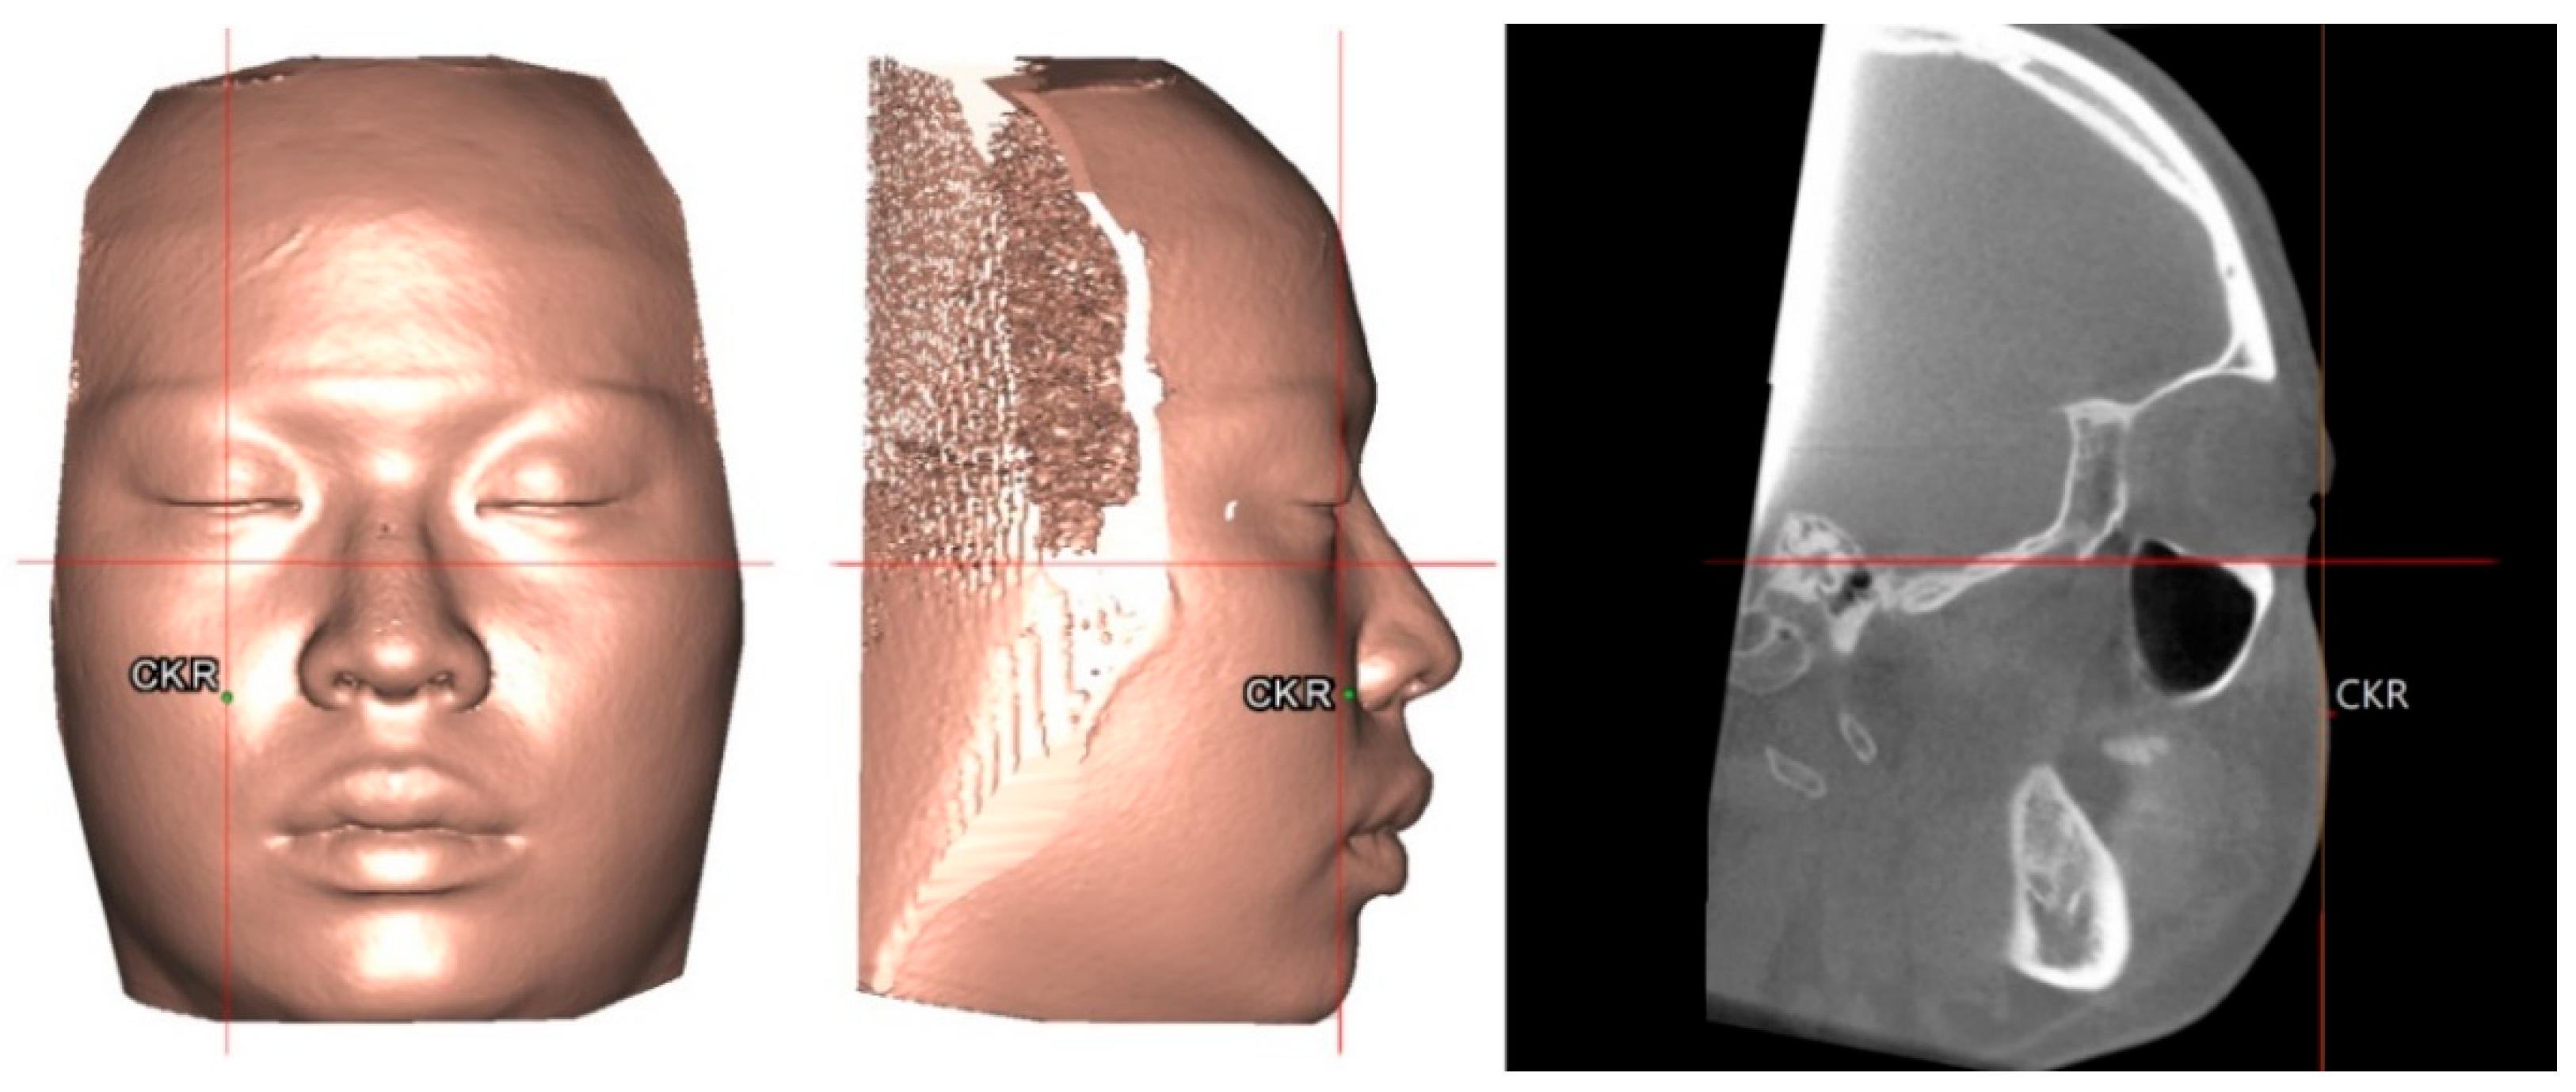

2.1. Three-Dimensional Image Acquisition and Processing

| Cheek mass | CK | The most convex point under infraorbital area relative to the perpendicular line from midpoint of upper eyelid to FH plane |